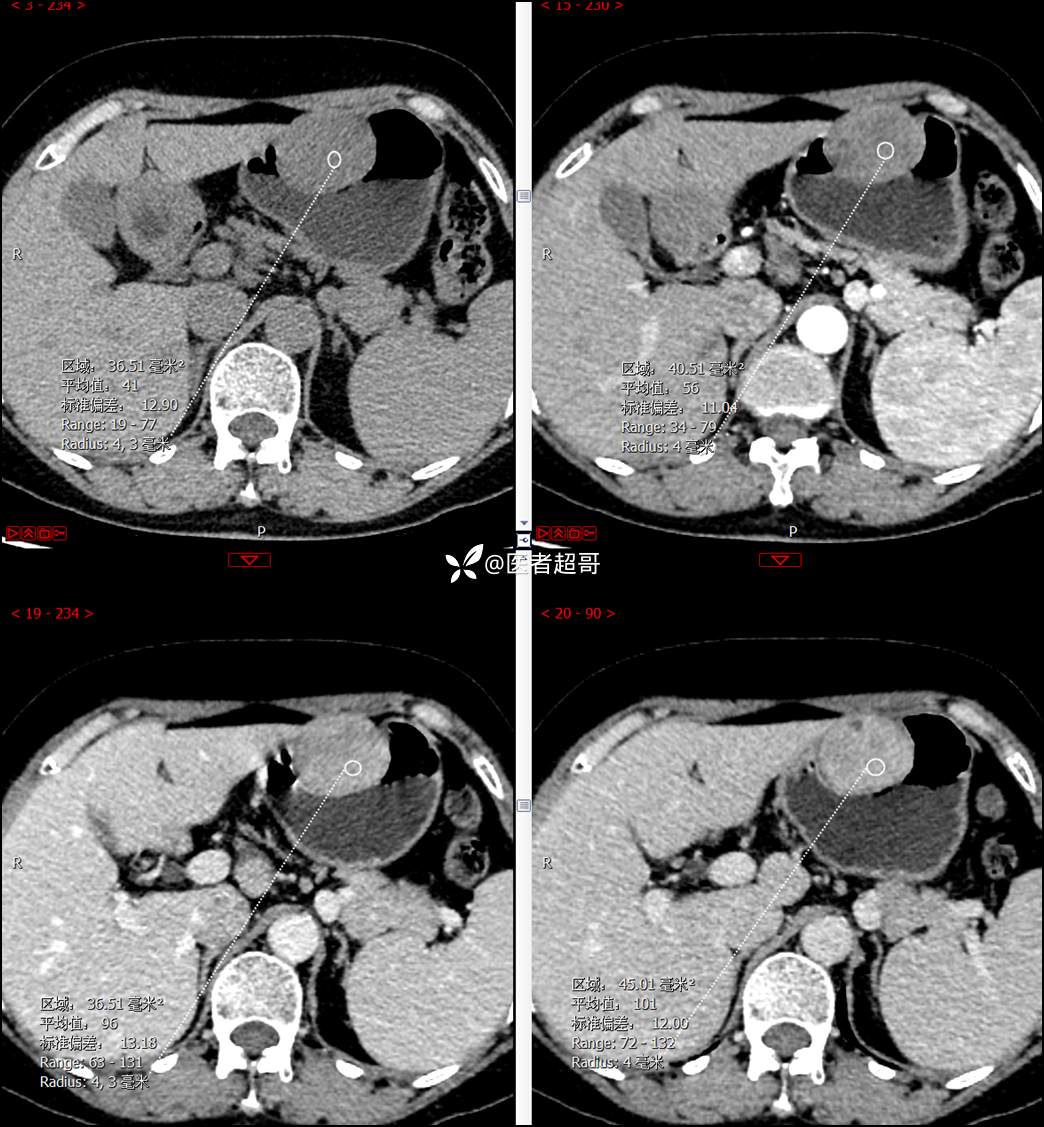

【影诊笔记759】胃体巨大隆起,间质瘤?神经鞘瘤?平滑肌瘤?请鉴别诊断!有结果!

患者半月前无明显原因及诱因出现上腹部疼痛不适,以夜间腹痛为主,无放射性疼痛,间断嗳气,无反酸烧心,无腹泻黑便,于我院门诊行胃镜显示:胃体前壁巨大隆起型病变。